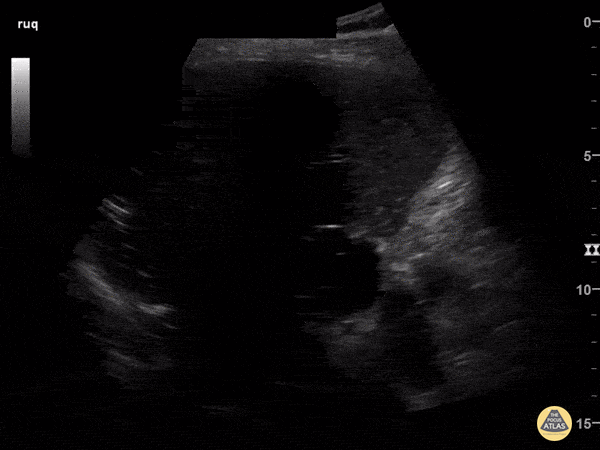

Biliary - Pneumobilia

82-year-old male with history of recurrent cholangitis presenting to the ED with abdominal pain. US imaging of the RUQ reveals presence of pneumobilia. Click here to read the full caption. Andrew Morris, M.D. Gaurav Patel, M.D. Vu Huy Tran, M.D. - Aventura Hospital & Medical Center, Emergency Medicine Program